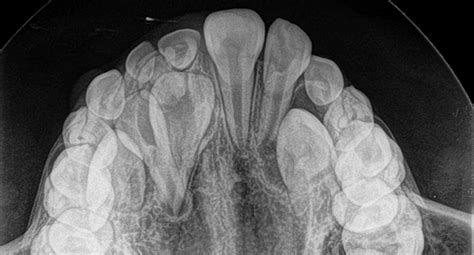

Asimismo, hay casos en los que encontramos dientes incluidos, también conocidos como dientes retenidos. Los dientes incluidos son piezas que no han salido pero se ven en la radiografía dentro del hueso. Suelen ser los caninos superiores, que se encuentran impactados en el paladar y suele ser frecuente su aparición en pacientes mayores de 15 años.